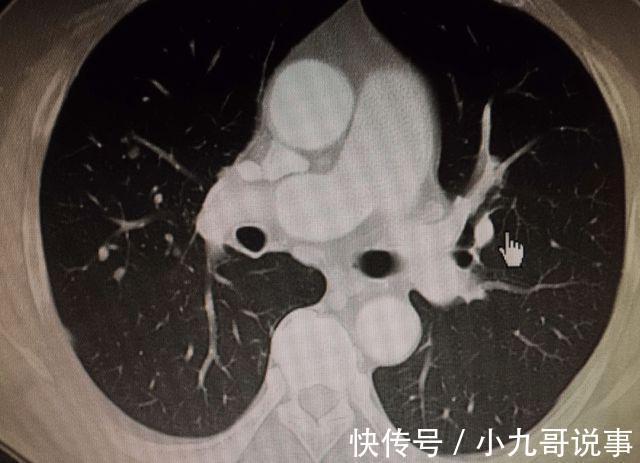

但是就在半年前,马大姐的服装店却开门了,而关门的原因也是因为马大姐在医院进行体检的时候,发现自己肺部出现了7毫米的肺结节。

虽然马大姐的结节是良性的,但是他自己也非常谨慎,生怕影响到身体健康,希望能够尽快住院治疗,并且早日让结节快速消散。